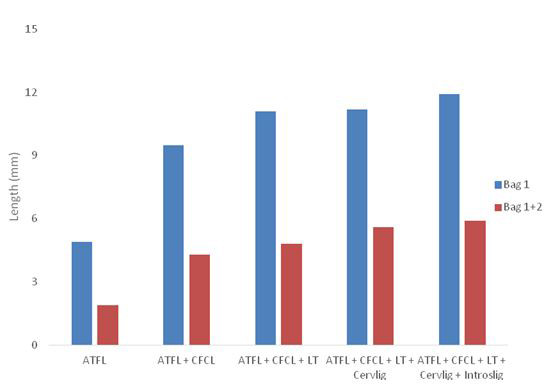

Une analyse cadavérique a été réalisée pour montrer une augmentation de la translation antérieure avec une section séquentielle des ligaments.

Les données cadavériques montrent une plus grande distance de translation antérieure avec ATFL et CFCL sectionnés. Avec la section successive des ligaments sous-taliens plus profonds, la translation antérieure était globalement plus importante, comme le montrent la figure 7 et les tableaux 4 et 5.

Une analyse cadavérique a été réalisée pour montrer une augmentation de la translation antérieure avec une section séquentielle des ligaments.

Les données cadavériques montrent une plus grande distance de translation antérieure avec ATFL et CFCL sectionnés. Avec la section successive des ligaments sous-taliens plus profonds, la translation antérieure était globalement plus importante, comme le montrent la figure 7 et les tableaux 4 et 5.

Figure 3 : Différence moyenne de translation antérieure en millimètres lorsque les forces antérieure (sac 1) et antérieure combinées aux forces postérieures (sac 1 + 2) sont appliquées aux cadavres.

En raison du nombre limité de cadavres (n = 8), il est difficile d'obtenir un résultat significatif.

Cependant, chaque cadavre présentait en moyenne une augmentation de la translation antérieure avec successivement plus de ligaments sectionnés et une réduction absolue de la translation antérieure de la sous-talienne avec une stabilisation appliquée au niveau du talus. Ces données cadavériques corroborent les données cliniques selon lesquelles le MADT pourrait être utile sur le plan clinique pour évaluer l'instabilité sous-talienne en complément de la radiographie de stress.